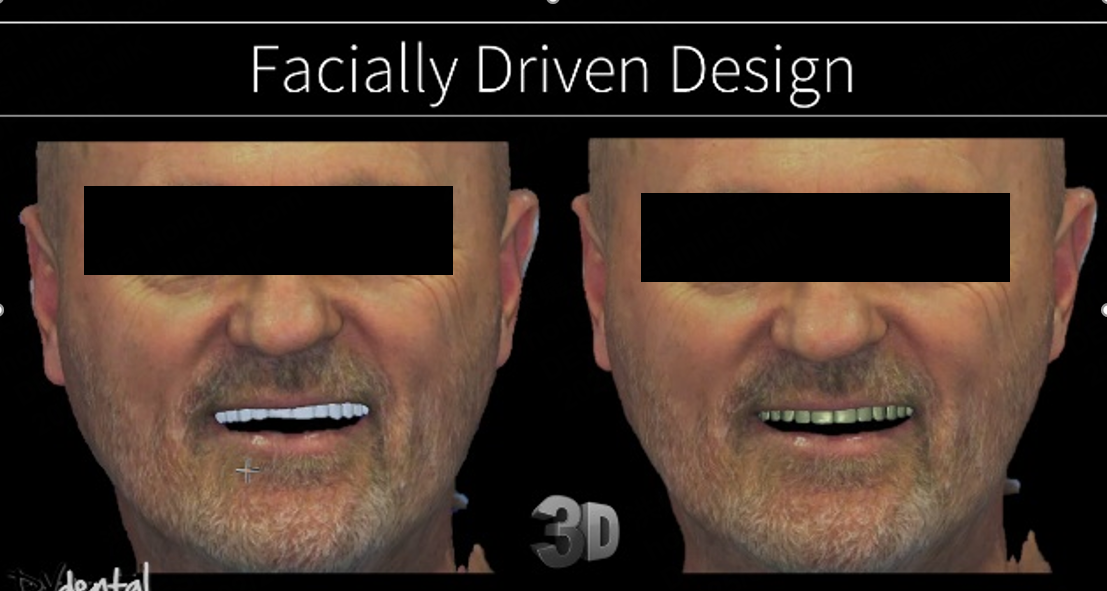

Additionally, due to the skewed smile line and unattractive appearance of the previous maxillary prosthesis, the patient expressed a desire for a more aesthetically pleasing design for the new restoration. To achieve this, we will use SHINING3D’s MetiSmile facial scanner to capture the patient’s facial data and use this data as a reference for smile design.

3. Design in exocad

After the capture process is done, we send everything to the lab. The lab mounts the data on the virtual articulator with the help of the face-scan, and designs a facially driven prosthesis for the upper jaw according to the patient’s needs. The integration of the dynamic bite within the CAD software allowed us to finalize our design functionally.